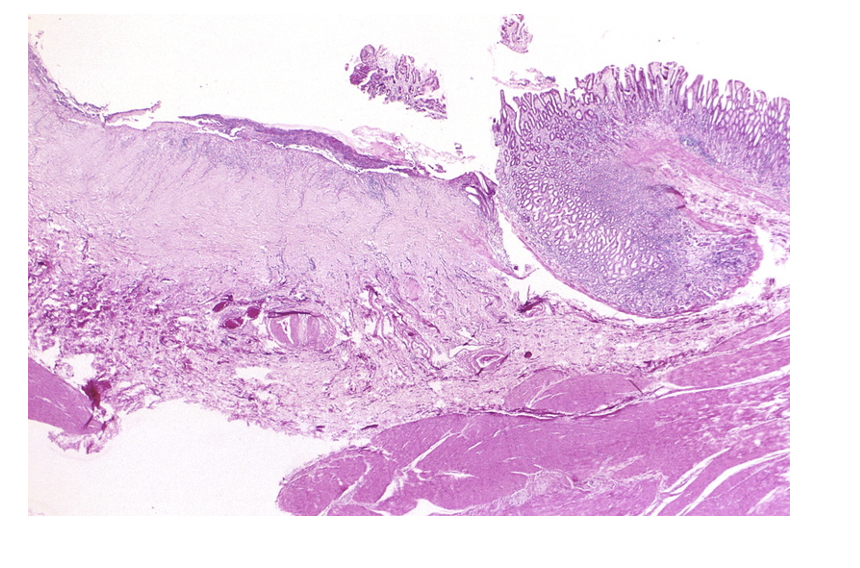

What is shown in this image?

Ulceration of GI mucosa

What is an ulcer? What differentiates an ulcer from an erosion?

Depth of the mucosal break. An ulcer penetrates the muscularis mucosae whereas an erosion does not.

A peptic ulcer is the focal destruction and loss of gastric or duodenal mucosa, the sub-mucosa, and frequently the underlying muscularis mucosae. A perforating ulcer is an ulcer that perforates through the entire wall of the stomach or duodenum.